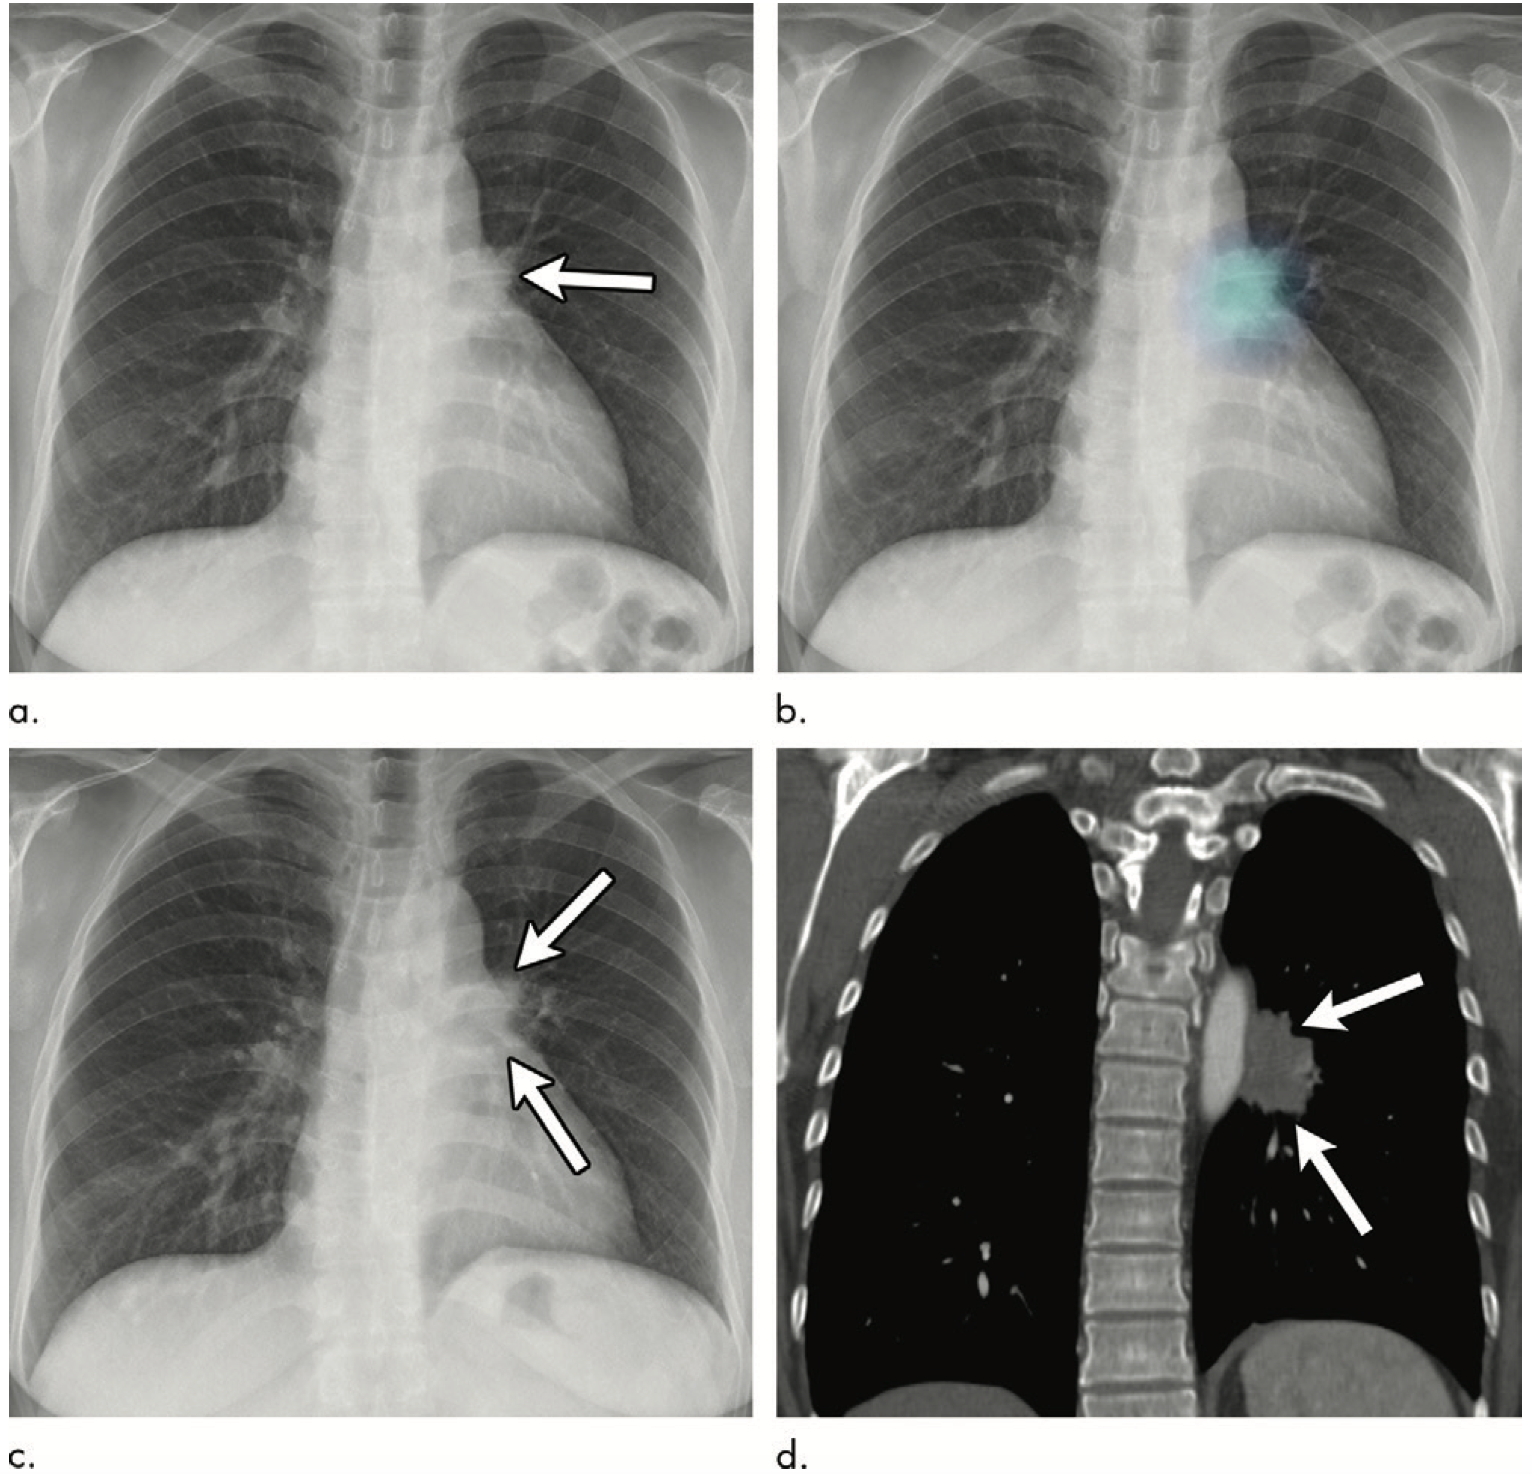

In addition, observers pinpointed more of the previously overlooked cancers when using the DLAD – 53 percent with compared to 40 percent without – and they also recommended chest CT for more patients with overlooked lung cancers when using the algorithm. For the patients who had actionable lung cancers, CT recommendations rose from 54 percent without the DLAD to 71 percent with it. Suggestions for follow-up CT scans in the healthy control group did not change, according to Jang’s team.